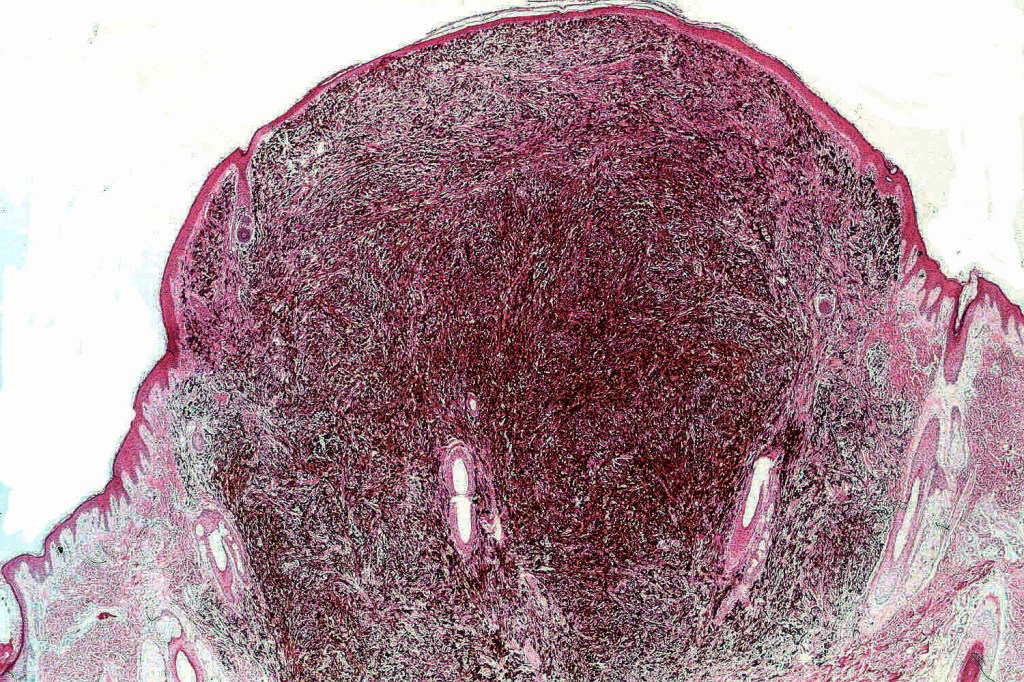

•Wedge shape or less often plaque like silhouette

•Commonly associated with marked acanthosis/pseudoepitheliomatous hyperplasia although much less commonly, the epidermis is strteched over the lesion